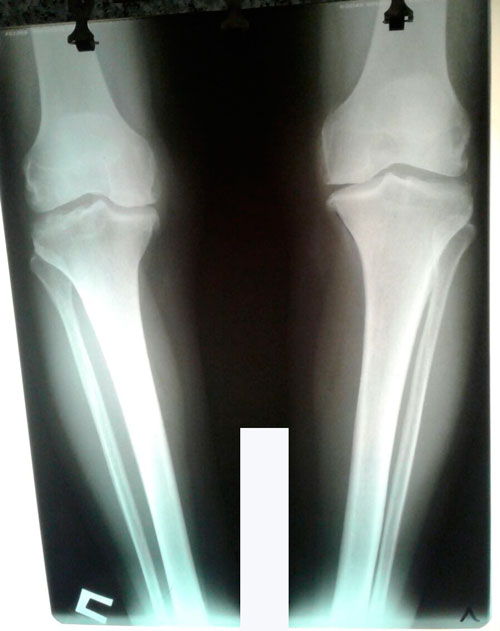

Исходник - 60 лет.

Дата операции 23.05.2017г.